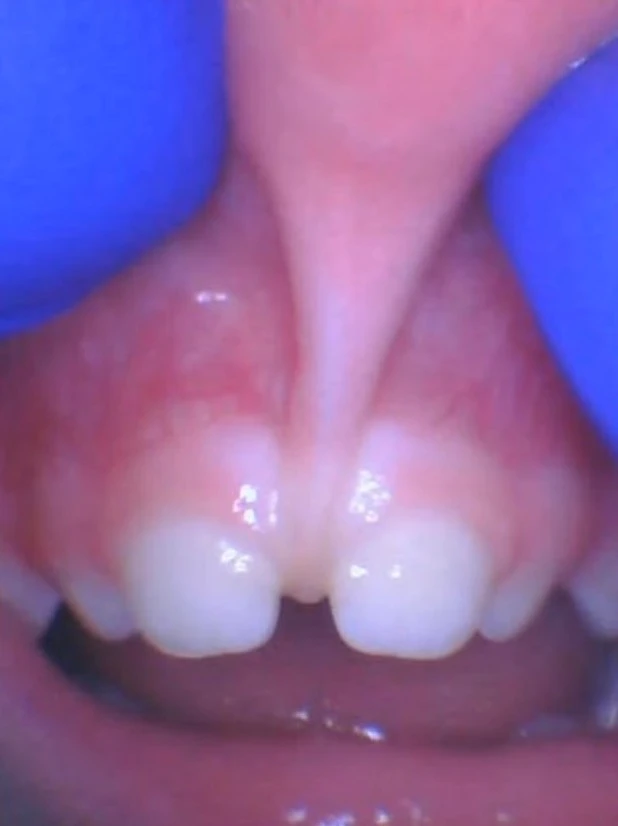

2. In toddlers, we treat lip-ties because of difficulty or fighting when brushing the teeth, a large gap or diastema in the teeth, and their teeth don’t show when they smile. We also treat it to help with B, P, M, and W sounds, and it can even help with nasal breathing once that tissue is released. Some children even have trouble eating from a spoon and flip it over, and after the lip-tie is corrected, parents report they can eat from a spoon normally.

Older children tolerate the procedure very well, and the best age to complete the lip-tie procedure for gap closure is either before 18 months old or around 7-8 years old when the incisors erupt. But if there are current symptoms (trouble brushing the teeth, etc.), it can be performed at any age. We use a numbing jelly, as well as a small injection of lidocaine to fully numb the area in older children who are cooperative.